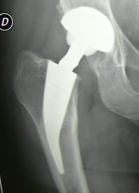

Come è fatta una protesi

La protesi è composta di quattro parti: la prima (lo stelo) è di titanio e viene incastrata nel femore precedentemente preparato; la seconda (la testina), di titanio o di ceramica, ha forma di sfera e permette una am

pia gamma di movimenti; la terza (la cupola), di forma emisferica, si fissa nel bacino ed è anch’essa di titanio; la quarta (l’inserto) si interpone fra la sfera e la emisfero ed è di ceramica o di polietilene.

Questi componenti permettono di riprodurre i movimenti naturali con pochissimo attrito tra di loro, evitando così un’usura del materiale.

Per ridurre al minimo questo rischio da molti anni utilizzo una mini-protesi la cui caratteristica, come dice il nome, è di essere molto più piccola di quelle più usate. Il grande vantaggio è che a parità di efficienza è necessario tagliare poco osso per impiantarle così che la riserva per il futuro è molto più grande! Nei rari casi in cui ho dovuto sostituirla dopo molti anni dalla prima operazione, ho potuto mettere una protesi “normale” senza dover ricorrere a quelle di dimensioni maggiori che spesso si usano.